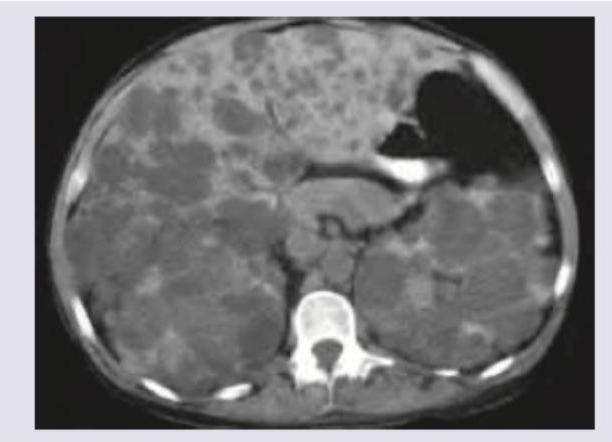

A 30-year-old hypertension patient presents with flank pain. CT abdomen was performed. All are true about the condition shown except?

Explanation: ***Bilateral kidney transplantation is the treatment of choice*** - While kidney transplantation is the **definitive treatment** for end-stage renal disease in ADPKD, it's not always bilateral. A single kidney transplant is often sufficient. - The image shows **polycystic kidneys and liver**, characteristic of **Autosomal Dominant Polycystic Kidney Disease (ADPKD)**. This condition often leads to **end-stage renal disease**, but a bilateral kidney transplant is not the primary intervention for all patients or the immediate treatment for flank pain. *Autosomal dominant disorder* - **ADPKD** is indeed an **autosomal dominant genetic disorder**, meaning only one copy of the defective gene is needed to cause the disease. - This genetic inheritance pattern explains the widespread occurrence of **cysts in the kidneys and liver**, as seen in the CT scan. *Chromosome 16 and 4 are involved* - The most common forms of ADPKD are linked to mutations in the **PKD1 gene on chromosome 16** (about 85% of cases) and the **PKD2 gene on chromosome 4** (about 15% of cases). - These genetic mutations lead to the development of numerous **cysts in the kidneys and other organs**. *Most common cause of death is cardiovascular causes* - **Cardiovascular complications**, such as **hypertension, left ventricular hypertrophy, and cerebral aneurysms**, are the leading causes of morbidity and mortality in ADPKD patients. - The patient's history of **hypertension** is a common early manifestation and a significant risk factor for these cardiovascular outcomes.